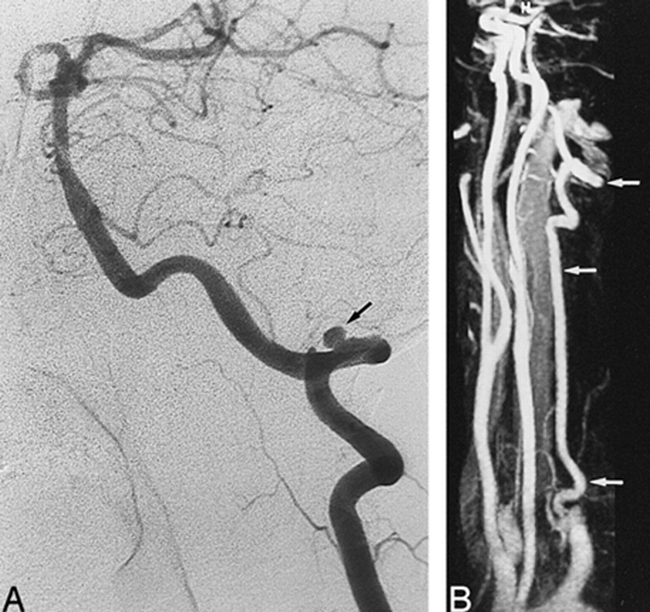

A 39-year-old man with neck pain and Wallenberg's syndrome.

A, Arch aortogram shows a small left VA (arrow), whereas the right VA is not visible.

B, Contrast-enhanced MR angiogram, obtained at 2 months, shows complete recanalization of the right VA, with a fusiform pseudoaneurysm in its intradural segment (arrow).

C, Contrast-enhanced MR angiogram, obtained at 6 months, shows a normal aspect of the right VA (arrow), with a complete resolution of the pseudoaneurysm.

D, T1-weighted MR image, obtained at 9 days, shows a typical aspect of dissection of the intradural segment of the right VA with a crescentic high signal (arrow) surrounding a narrowed signal void (arrowhead).

E, T1-weighted axial MR image, obtained at 6 months, shows a spontaneous resolution of the mural hematoma of the right VA (arrow).